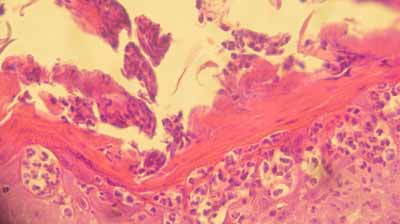

Il montre une hypergranulose diffuse et une hyperkératose parakératosique diffuse, se traduisant par la formation d’une couche cornée parakératosique, diffuse très compacte, devenant superficiellement, sur certaines biopsies, pustuleuse, avec très en surface de cette couche cornée, possibilité d’accumulation d’un feutrage bactérien abondant.

cas-de-parakeratose-granulaire9Photo 9 : Hypergranulose et parakératose

cas-de-parakeratose-granulaire10Photo 10 : Vue rapprochée de l’hypergranulose

de la couche granuleuse